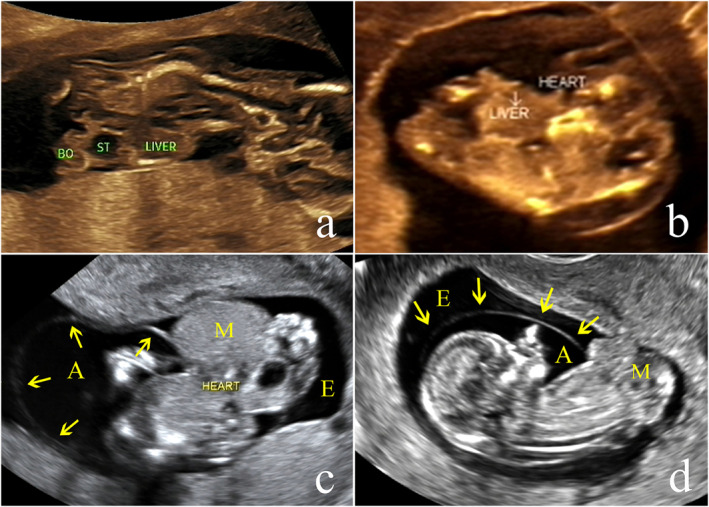

本研究旨在探讨产前超声对妊娠期肢体体壁复合体(LBWC)的诊断价值,提高对LBWC的认识,用于早期超声诊断。回顾性分析郑州大学第三附属医院2014 ~ 2024年107例LBWC(以妊娠早期诊断为主)的超声资料及随访结果。对LBWC的超声特征和胎儿核型进行评价。该队列包括107例LBWC胎儿(90例单胎和17例双胞胎)。典型的超声表现为腹壁严重缺损、重度脊柱后凸、肢体异常、神经管缺损、短脐畸形伴单动脉。值得注意的是,38例清楚地显示胎儿挤压器官位于胚胎外细胞。20例基因检测(7例CNV-seq, 12例CMA, 1例核型)18例结果正常,其余2例病因不明。在4例双胎妊娠中进行了选择性胎儿减位术,成功分娩了健康的新生儿;其余病例均行终止妊娠。LBWC是一种严重的发育畸形,预后很差。超声检查可以在妊娠早期发现,在产前筛查和妊娠管理中显示出关键的诊断价值。

This study aims to explore the diagnostic value of prenatal ultrasound in limb body wall complex (LBWC) during pregnancy and to improve the understanding of LBWC for early ultrasound diagnosis. The ultrasound data and follow-up results of 107 cases of LBWC (predominantly diagnosed in the first trimester) from the Third Affiliated Hospital of Zhengzhou University between 2014 and 2024 were retrospectively analyzed. The ultrasonographic features and fetal karyotype of LBWC were evaluated. The cohort included 107 LBWC fetuses (90 singletons and 17 twins). The typical ultrasonographic features were a major abdominal wall defect, severe kyphoscoliosis, limb abnormalities, neural tube defects, and a malformed short umbilical cord with a single artery. Notably, 38 cases clearly demonstrated fetal extruded organs located within the extraembryonic celom. Genetic testing (7 CNV-seq, 12 CMA, 1 karyotype only) in 20 cases revealed normal results in 18 without clear cause and effect in the remaining two. Selective fetal reduction was performed in four twin pregnancies, resulting in successful delivery of healthy neonate; all remaining cases underwent pregnancy termination. LBWC is a severe developmental malformation with a very poor prognosis. Ultrasonography enables early detection during the first trimester, demonstrating critical diagnostic value in prenatal screening and pregnancy management.